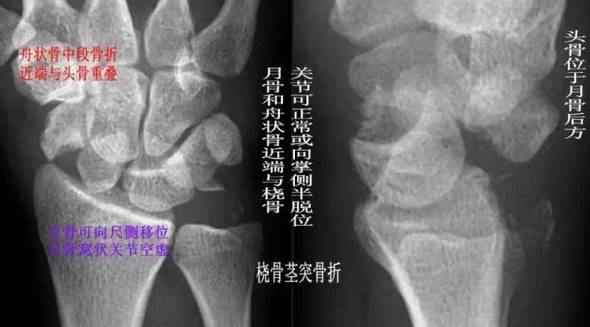

(4)经舟骨月骨周围脱位:表现为月骨周围脱位伴舟骨骨折,且骨折远段随头骨向后脱位,而骨折近段与桡骨、月骨关系保持正常。

经舟骨月骨周围脱位影像特点